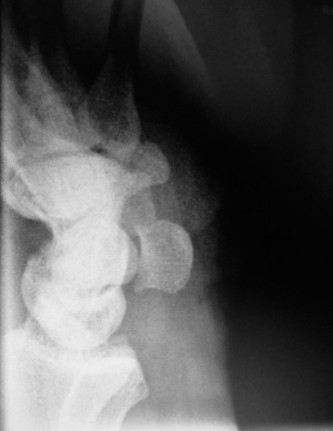

Use 1-2ICSRA to revascularize the scaphoid? CASE 3 ### A patient is brought into the emergency room following a motor vehicle accident. He complains of severe pain in his wrist. Physical examination reveals a tender and swollen wrist. X-rays (Figs. 3–5A–B) are as follows. What is your diagnosis?

Figure 3–5 A–B. (©) Sunil Thirkannad and Christine M. Kleinert.

The correct answer is (D). This x-ray reveals a perilunate injury of the wrist. It is important to be aware of the various radiological parameters that reveal disruption of carpal alignment. Literature suggests that a perilunate injury is missed as much as 25% to 40% of the times. Which radiological signs of perilunate injury can be seen on the above Figs. 3–5A–B .

The correct answer is (E). All three radiological signs are seen on this x-ray. Triangle sign refers to the shape of the lunate seen on the PA view. A normal, well located lunate looks like a tilted trapezium. A triangular-shaped lunate suggests that it is in a hyperflexed position. In the lateral view, a subluxated and volar-tilted lunate has the appearance of a “spilt teacup.” In the above x-ray, Gilula’s first and second lines are broken.